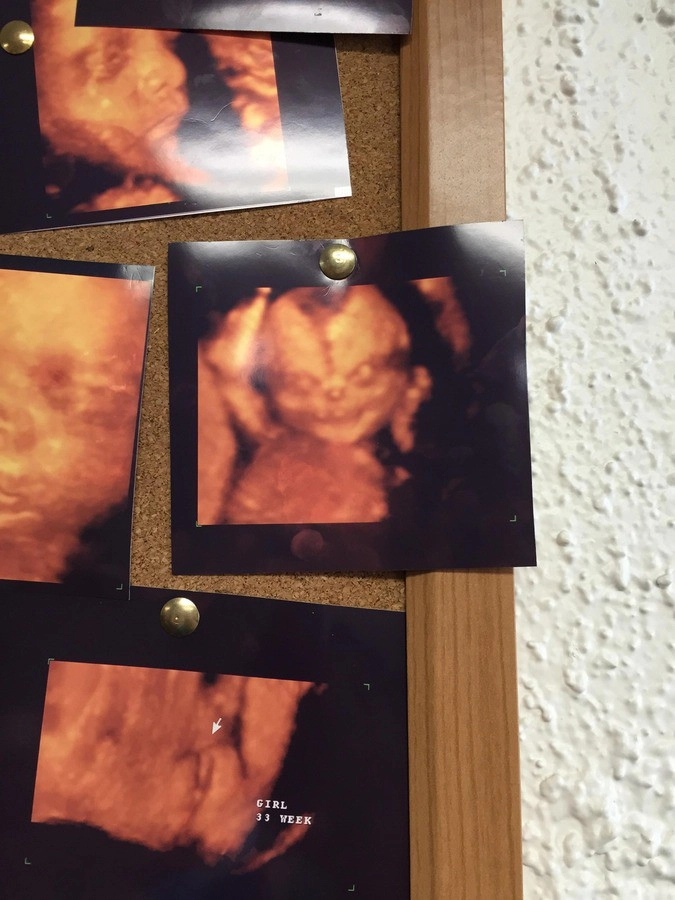

Пользователи портала Reddit обсуждают изображение ребенка, полученное с помощью ультразвука.

Автор фото утверждает, что снимок висел на стене медицинского центра, куда он пришел вместе с женой.

«Мы с женой собирались сделать 4D-УЗИ своего нерожденного ребенка. Увидели картинку (висящую на стене — ред.). Передумали», — сообщил мужчина.

По его словам, на стене висело множество снимков, однако они были однотипными. Этот же особенно выделялся и внушал страх.

«Я только могу себе представить ужас, который испытали родители этого ребенка, когда увидели его лицо во время процедуры», — поделился автор фото своими ощущениями.

Фотография вызвала бурные обсуждения на портале.

«Первыми словами этого ребенка будут следующие: души, дайте мне души», — написал один из пользователей.

«Что у него в руке, бутылка пива?», — задался вопросом другой.

Пользователи сравнивали персонажа на фото с антихристом и куклой Чаки из фильма ужасов, поздравляли родителей со скорым «рождением демона», а также заметили, что у ребенка, вероятно, «бабушкин нос».